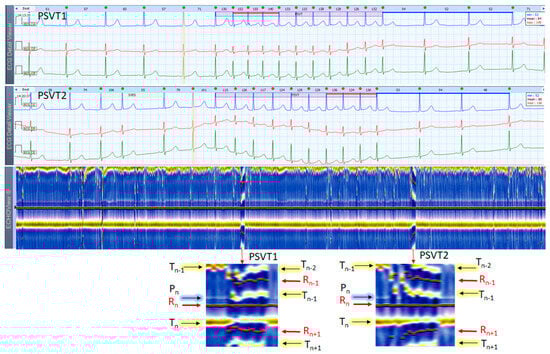

3.5. Paroxysmal Supraventricular Tachycardia Cases

This section interprets 3-lead Holter ECG strips and the corresponding ECHOView images (ECG lead 1) of three patients presenting short runs (≤10 s) of paroxysmal supraventricular tachycardia (PSVT) at the background of predominant NSR for most of the record (Figure 10, Figure 11 and Figure 12). These arrhythmias could occur at any age and are more common among women. The ‘slow-fast’ AVNRT is the most common form of PSVT, particularly in otherwise healthy hearts. It is caused by a reentrant circuit, created between two pathways (‘slowly’ and ‘fast’ conducting pathways) in or around the AV node. When the HR is too high, it is sometimes difficult to differentiate PSVT from high-rate SINT, especially in people without underlying cardiac or non-cardiac diseases. In patients with overt cardiac diseases or other pathological conditions (for example hyperthyroidism), PSVT must be differentiated not only from sinus tachycardia (common in such conditions) but also from high-rate AFL/AF. ECHOView color maps in such cases present quite distinctive patterns of PSVTs compared to NRS and SINT (Figure 6, Figure 7 and Figure 8). The beginning and the end of the arrhythmia can be identified at a glance (Figure 10, Figure 11 and Figure 12). In addition, ECHOView may facilitate the differentiation of the different PSVT subtypes. In summary, ECHOView improves the reading of Holter recordings with PSVT by saving time to visually locate the arrhythmia episodes and refine the diagnosis of these typically short events.

The color-coded ECG amplitudes of sequential beats produce an intuitive trace of different intervals (PnRn, RnTn, Rn−1Rn, RnRn+1, etc.) in a visible image (width × height = 1740 beats × 1500 ms) within one ECHOView page. Without a specific measurement, this visual effect resembles the rendering of one-dimensional time trends of automatically measured ECG intervals. These trends show stable PnRn and RnTn intervals during the NSR part of the examples in Figure 4, Figure 5, Figure 6, Figure 7, Figure 8, Figure 9, Figure 10, Figure 11 and Figure 12. The trends are also informative for the RR-intervals (Rn−1Rn, RnRn+1) on a beat-by-beat basis that is helpful for identifying long-term HR changes in high-rate SINT (Figure 6, Figure 7 and Figure 8) and AFL (Figure 15), as well as rhythm, transitions NSR→ paroxysmal SVA (Figure 9), NSR→PSVT (Figure 10, Figure 11 and Figure 12), NSR→NSVT (Figure 10, Figure 11 and Figure 12), and AF→AFL→ST (Figure 16).